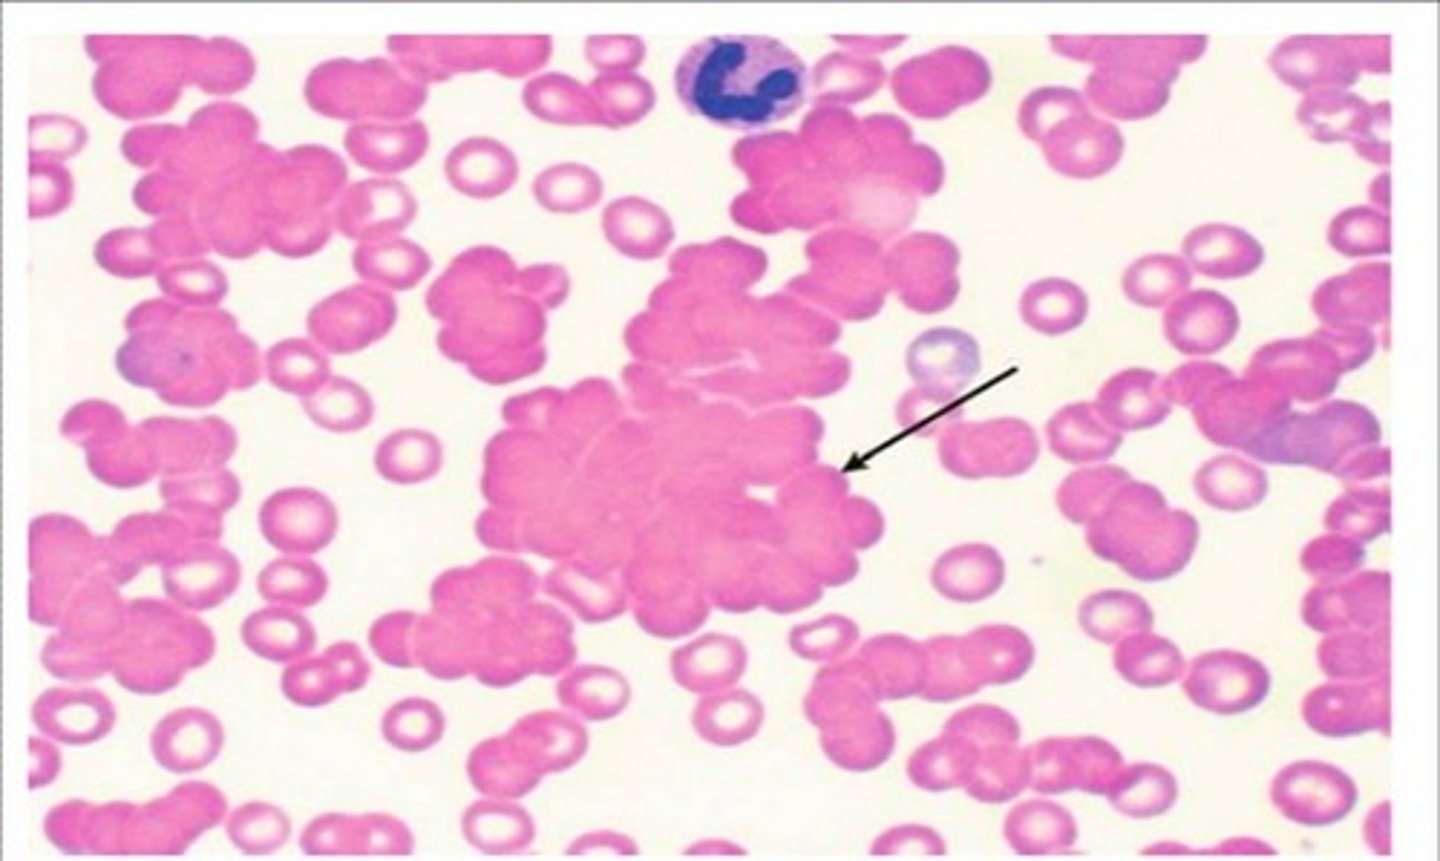

Painful blue fingers/toes, hemolytic anemia

Cold agglutinin disease (autoimmune hemolytic anemia caused by Mycoplasma pneumoniae, infectious mononucleosis, CLL)

Painful fingers/toes changing color from blue to white to red with cold or stress

Raynaud phenomenon (vasospasm in extremities)